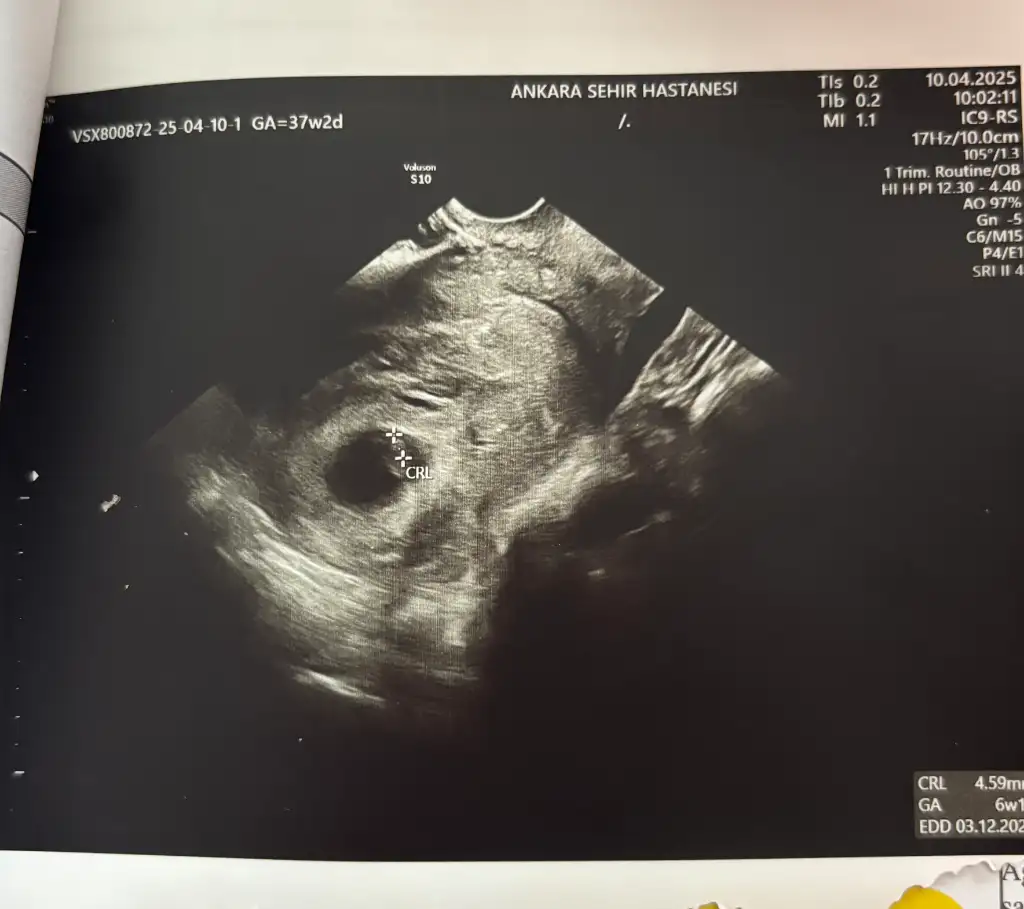

6 haftalik karından ultrasyon tahminde bulunabilir misiniz

Eklentiler

• IMG_20250312_112835.webp

IMG_20250312_112835.webp

31,3 KB · Görüntüleme: 70

• IMG_20250312_094215.webp

IMG_20250312_094215.webp

21,9 KB · Görüntüleme: 58

• IMG_20250312_094132.webp

IMG_20250312_094132.webp

44,2 KB · Görüntüleme: 73